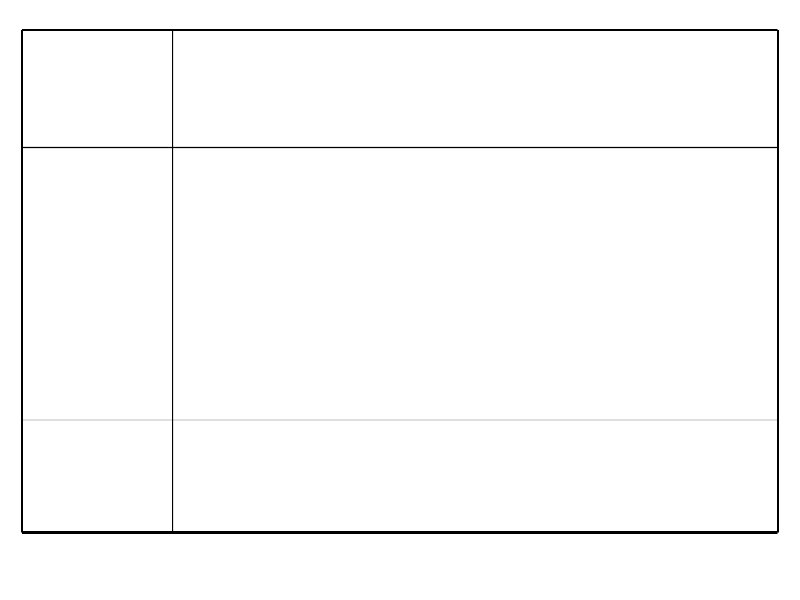

Диагностический алгоритм при неходжкинских лимфомах